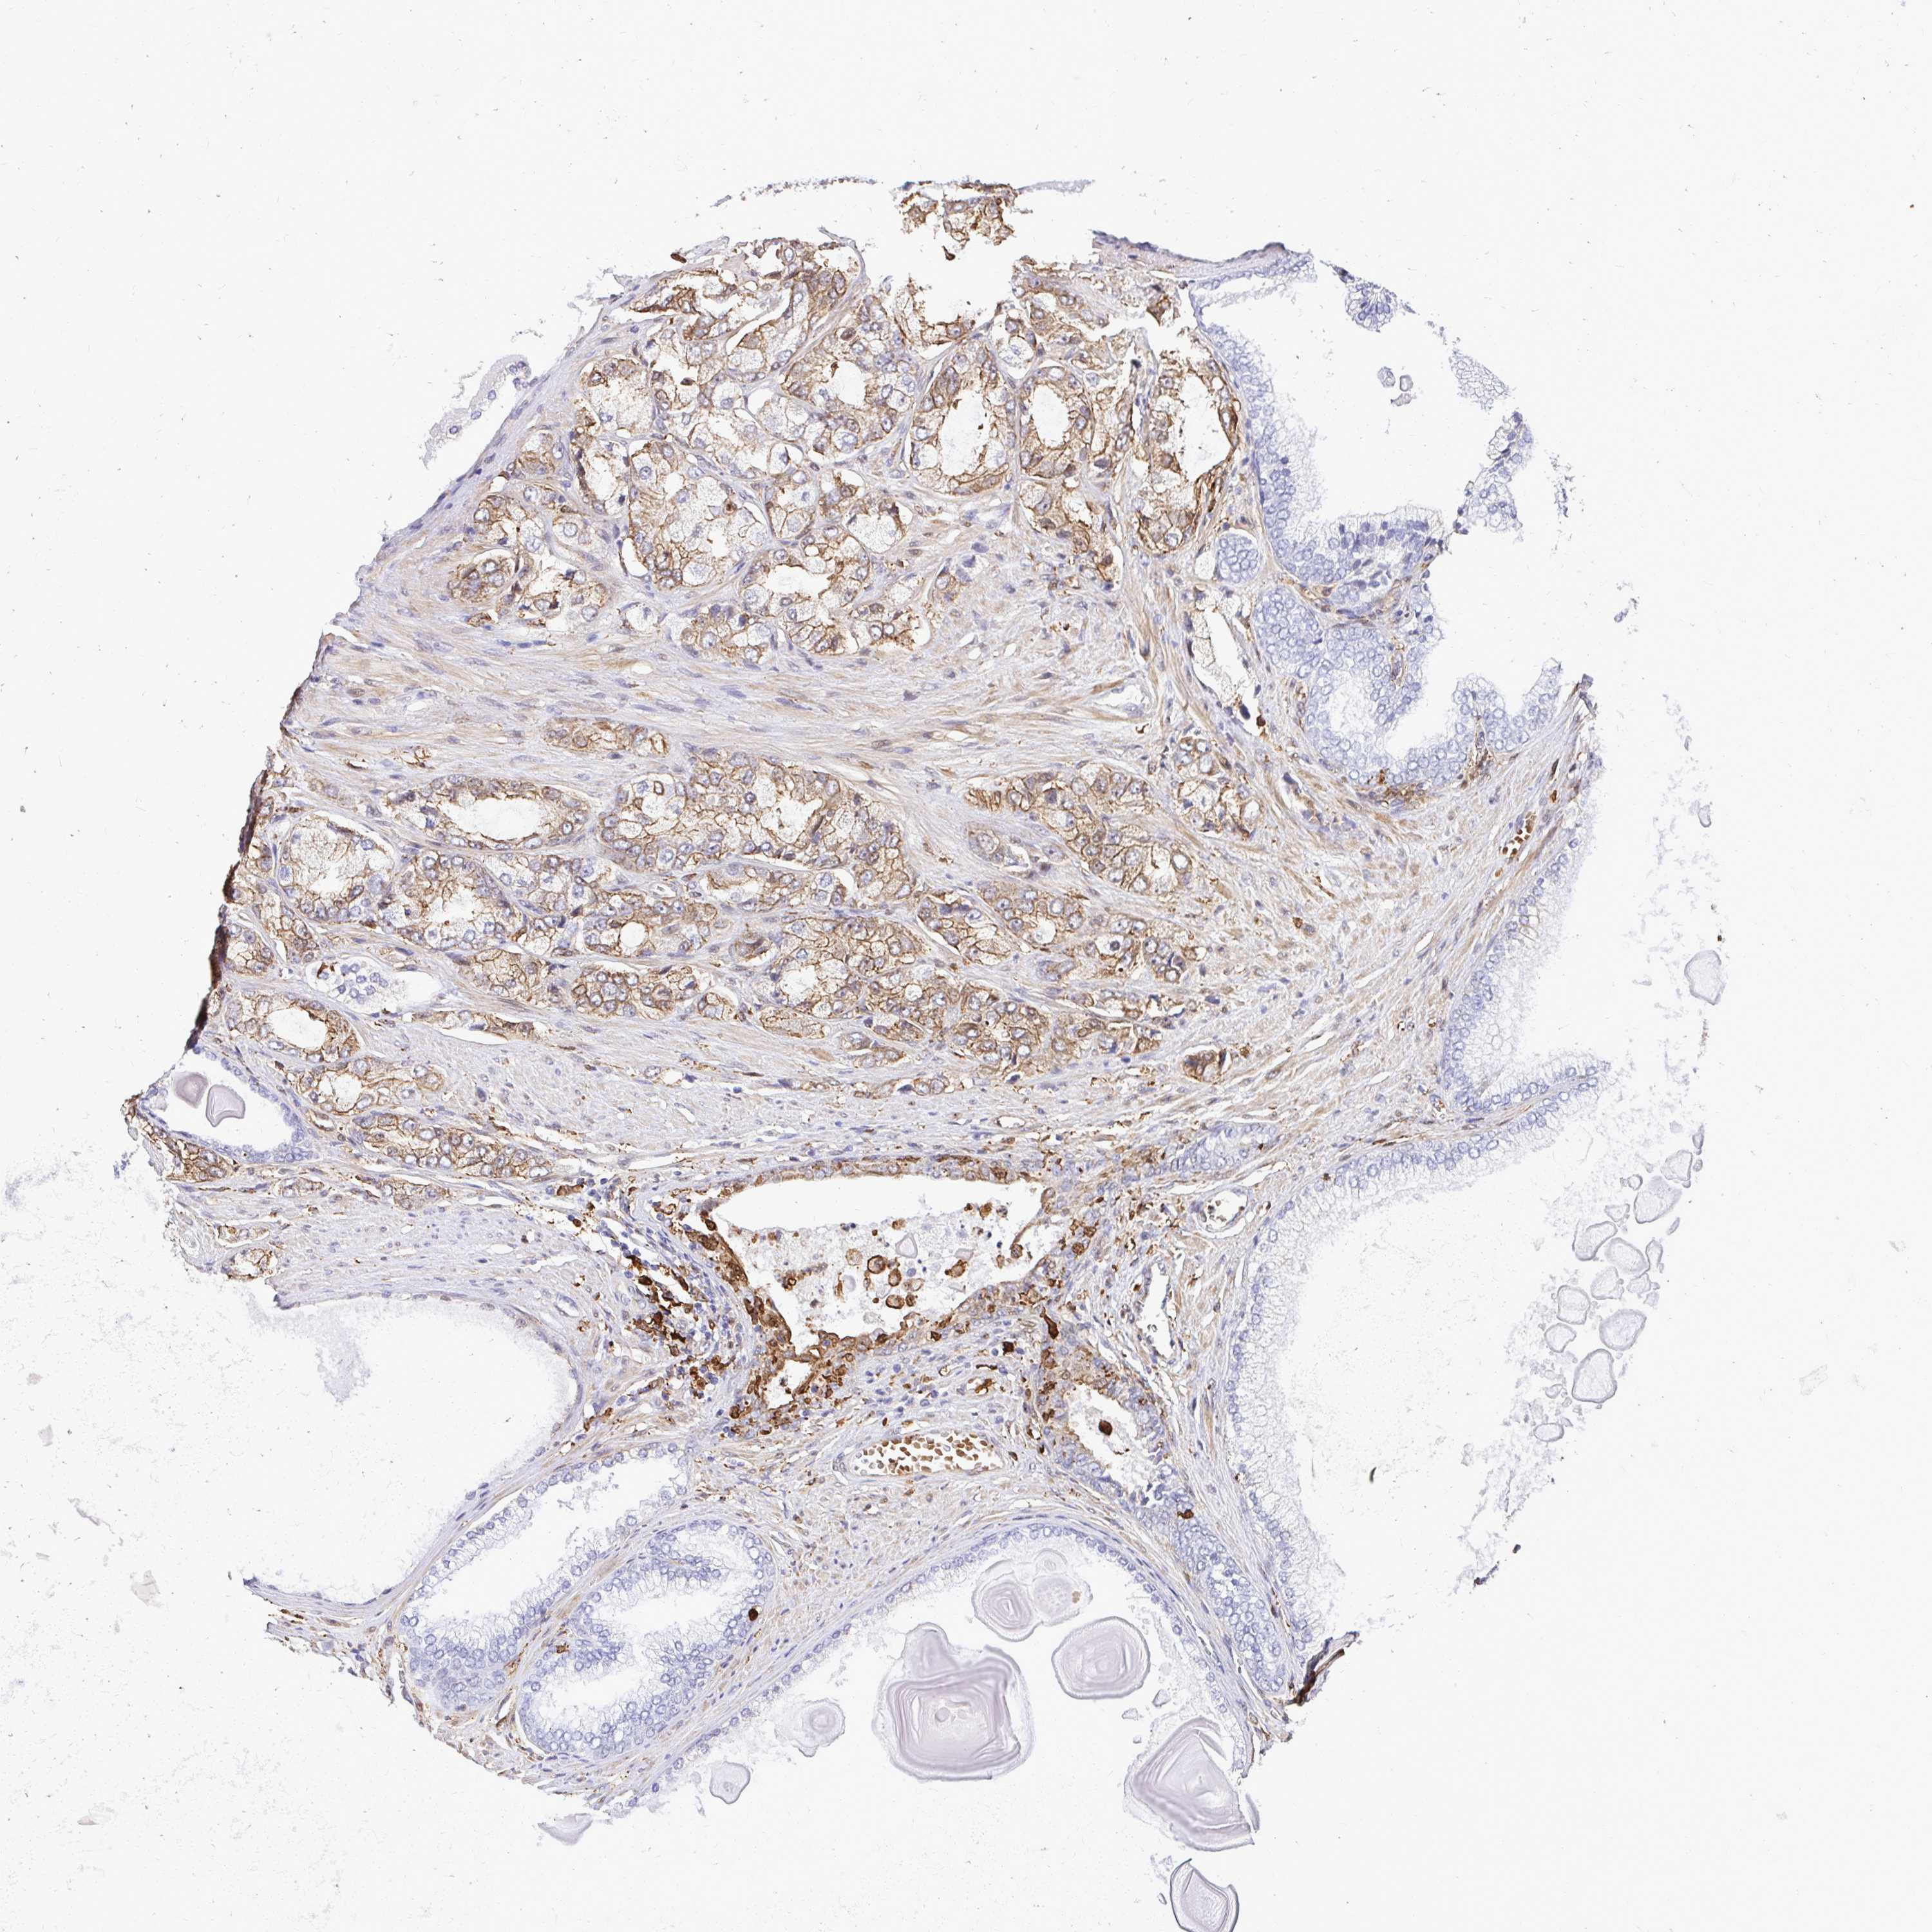

PROSTATE CANCER - Protein expressioni

A mouse-over function shows sample information and annotation data. Click on an image to view it in a full screen mode. Samples can be filtered based on level of antibody staining by selecting one or several of the following categories: high, medium, low and not detected. The assay and annotation is described here.

Antibody stainingi

Antibody staining in the annotated cell types in the current human tissue is reported as not detected, low, medium, or high, based on conventional immunohistochemistry profiling in selected tissues. This score is based on the combination of the staining intensity and fraction of stained cells.

Each image is clickable and will lead to virtual microscopy that enables deeper exploration of all samples and also displays staining intensity scores, fraction scores and subcellular localization as well as patient and tissue information for each sample.

Antibody HPA054026

Antibody CAB010823

Antibody CAB016728

Antibody CAB036009

Staining

High

Medium

Low

Not detected

Intensity

Strong

Moderate

Weak

Negative

Quantity

>75%

75%-25%

<25%

None

Location

Nuclear

Cytoplasmic/membranous

Cytoplasmic/membranous,nuclear

Adenocarcinoma, High grade

Adenocarcinoma, Low grade